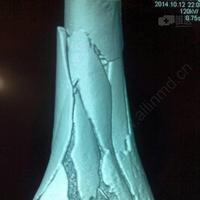

男45岁,胫骨远端粉碎性骨折

请教胫骨开放性粉碎性骨折的治疗

微创手术治疗胫骨干粉碎性骨折

粉碎性骨折

小腿粉碎性骨折图片

粉碎性骨折图片

粉碎性骨折x光

粉碎性骨折片子图片

粉碎性骨折x光片

什么叫粉碎性骨折图片